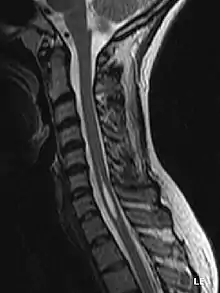

Siringomielia (syrinx/greacă/ = canal, tub, fistulă, mielos = măduvă)[1] este un termen generic care se referă la o afecțiune în care în măduva spinării apare un chist sau o altă formă de cavitate. Acest chist, numit Sirinx, se poate extinde și alungi de-a lungul timpului, distrugând măduva spinării. Leziunile provocate de chist în substanța cenușie din țesuturile învecinate pot provoca durere, paralizie, slăbiciune,[2], rigiditatea spatelui, ale umerilor și de asemenea, pierdere a capacității de a simți prin piele temperaturi estrem de ridicate sau coborâte, mai ales la mâini. Afecțiunea cauzează în general pierderea capacității de a simți durere și temperatura de-a lungul spatelui și în brațe. Fiecare pacient prezintă o combinație diferită de simptome. Aceste simptome de obicei variază în funcție de amploarea și de multe ori mult mai pregnant de locația sirinxului în măduva spinării. Siringomielia are o incidență estimată la 8,4 cazuri la 100.000 de persoane, simpromele apărând de obicei după adolescență, la vârste între 20 și 40 de ani. Semnele afecțiunii se dezvoltă,de obicei, încet, deși poate debuta brusc cu tuse, redoare, sau mielopatie. Peste 50% din cazurile de siringomielie sunt asociate cu malformația Arnold-Chiari de tipul I.